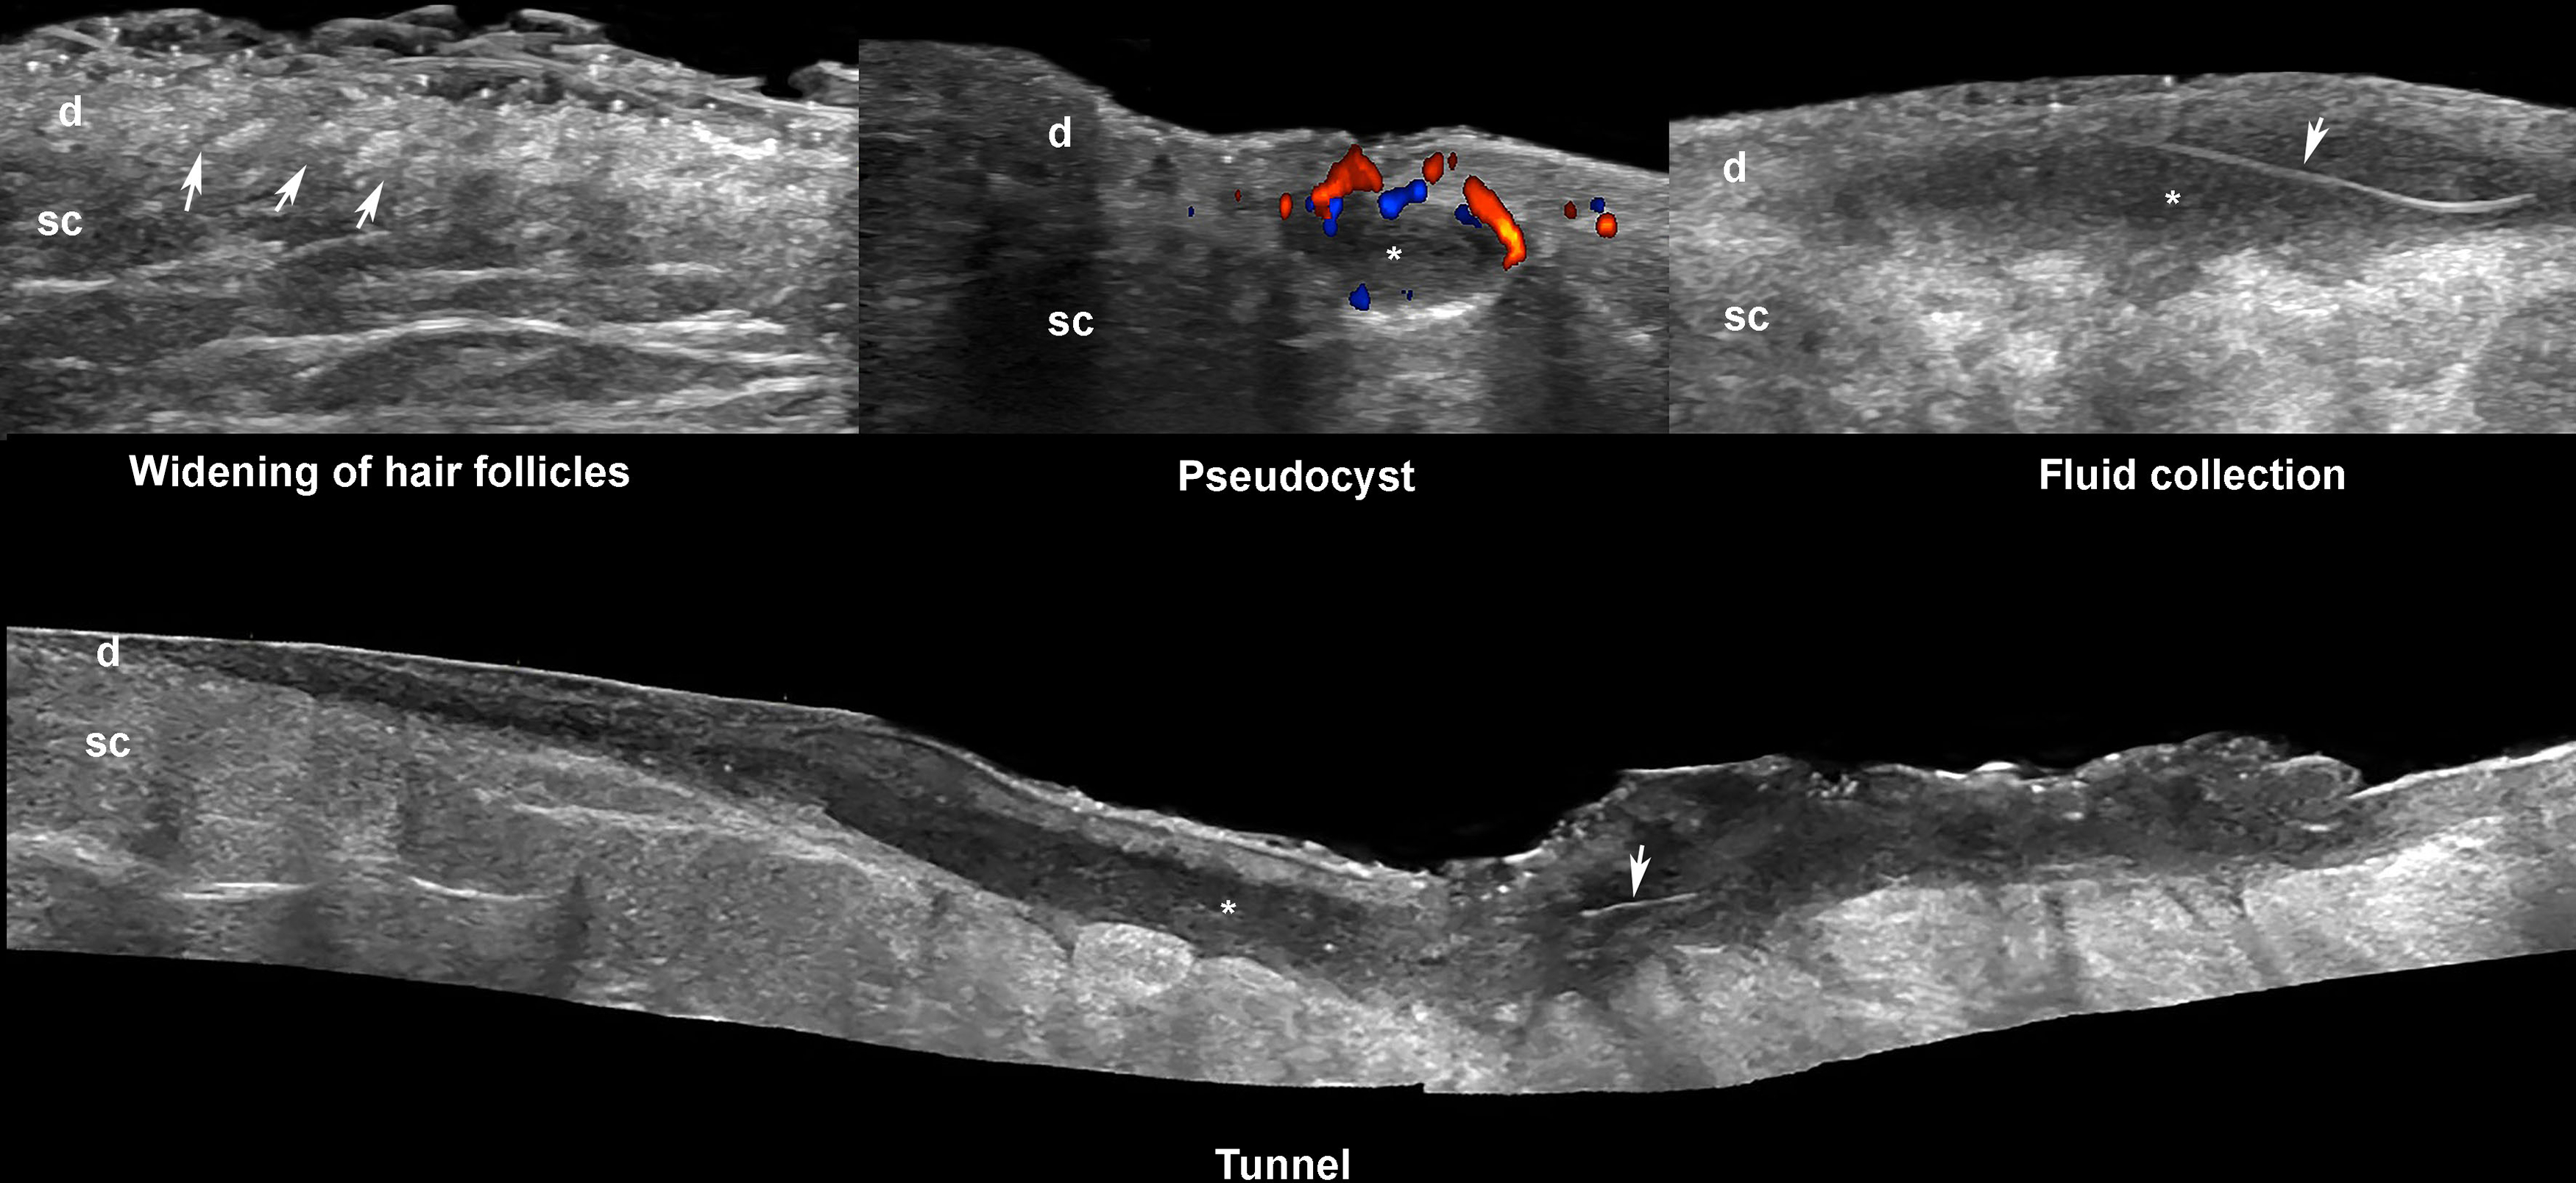

These devices are widely available and allow detection of subclinical lesions, scoring the severity of the disease, and the evaluation of the degree of inflammatory activity, besides other anatomical details.These key ultrasonographic signs are ( Fig. 6.6 ) b :

- 1.

Dilation of hair follicles

- 2.

Increased thickness and decreased echogenicity of the dermis

- 3.

Pseudocysts (i.e., round or oval-shaped anechoic or hypoechoic dermal and/or hypodermal nodule < 1 cm)

- 4.

Fluid collections (i.e., anechoic or hypoechoic sac-like dermal and/or hypodermal structures ≥ 1 cm connected to the base of dilated hair follicles)

- 5.

Tunnels, also called fistulous tracts (i.e., anechoic or hypoechoic band-like dermal or hypodermal structures connected to the bottom of dilated hair follicles), which can be communicated between them or not.